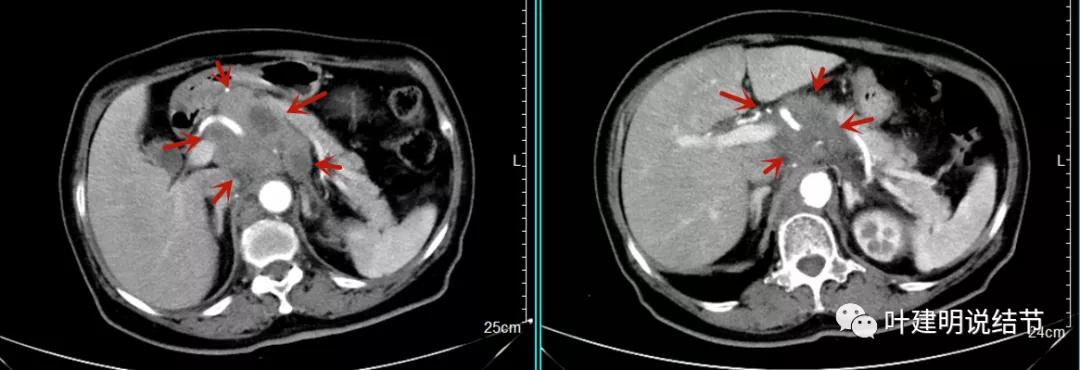

之后又再经过一个周期后的对比:

上图同样左侧是治疗前的,右侧经过2周期免疫加化疗后复查的,可见病灶缩小甚至超过9成。下面是治疗前与后来于6月底复查的:

可见经过4个多月的治疗,转移灶已经几乎看不出来了!目前患者无任何不适,正常进食,也无腹部症状或体征,仍在持续特瑞普利单抗维持治疗中。我们期待其更长久的获益与持久的疗效,为其他晚期食管癌积累自己的实战经验(开会或文献上别人的介绍没有自己遇到的如此直观,也没有如此深的印象。所以我一直觉得临床经验,尤其自己亲身经历积累的经验才更有说服力,也更有感受)。